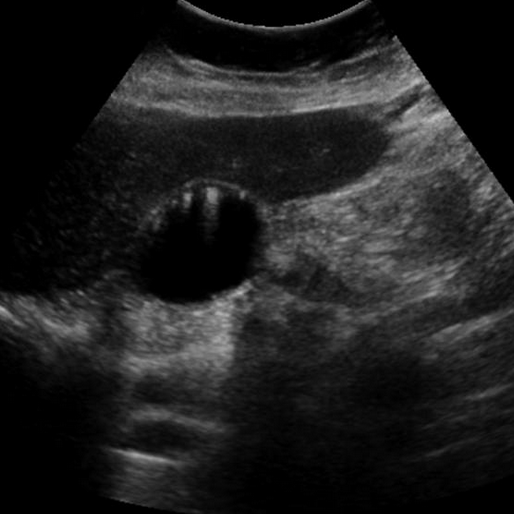

• Accumulation of cholesterol crystals in gallbladder with formation of GB wall out-pouchings called Rokitansky-Aschoff sinuses

• Comet-tail artifact is highly suggestive of diagnosis

• Looks like a dot with streaky line following it